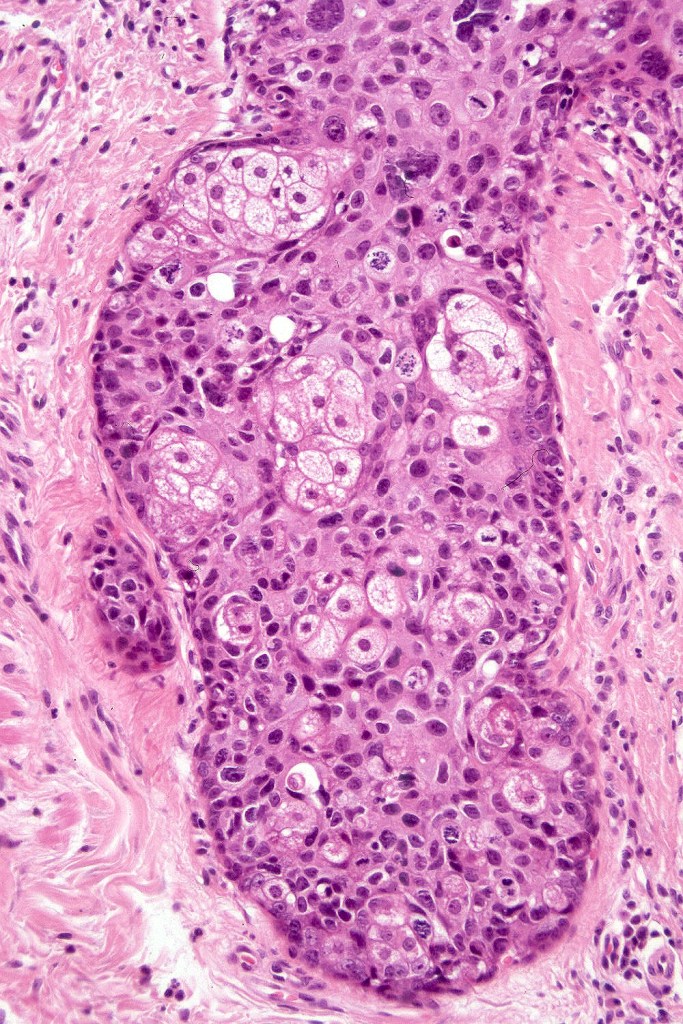

•Hyperkeratotic/hyperplastic actinic keratosis represents the prototype-alternating hyperkeratosis & parakeratosis- the former overlies the follicular & sweat duct ostia (Freudenthal funnel) while the latter overlies the interadnexal dysplastic epithelium & ranges from basal cell layer though to full thickness dysplasia (Bowenoid actinic keratosis); budding from the epidermis is a common finding; dysplastic epithelium commonly forms a mantle around the follicles and superficial sweat ducts

•Variable lack of maturation, nuclear irregularity, pleomorphism & mitotic activity